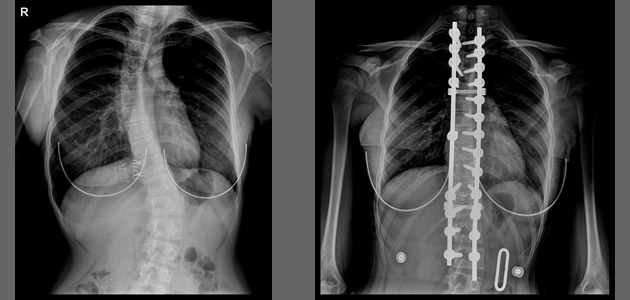

Cerrahi

Cerrahi operasyonlar genellikle sadece skolyozun aşırı durumlarında yapılır. Cerrah omurlar arasından bir ya da daha fazla disk çıkarabilir ve daha sonra çubuklar, barlar veya teller yardımı ile omurga stabilize haline getirilir.